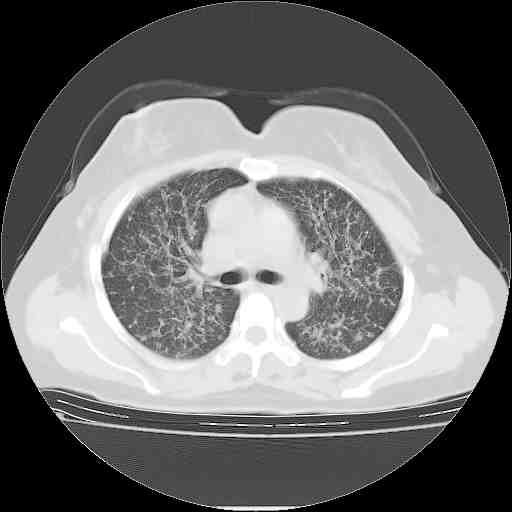

支气管血管束粗而乱,考虑肺癌肺内淋巴管转移,右侧乳房第一二层软组织成份较左侧多,不会有问题吧?

标准的细支气管肺泡癌呀!治疗后病情有所控制,也没治愈的迹象!

应该是比较典型的细支气管炎,4个月的时间不说明问题;有时候疾病是有个相对稳定期的,如果喝10元一斤的茶叶估计也会这样。